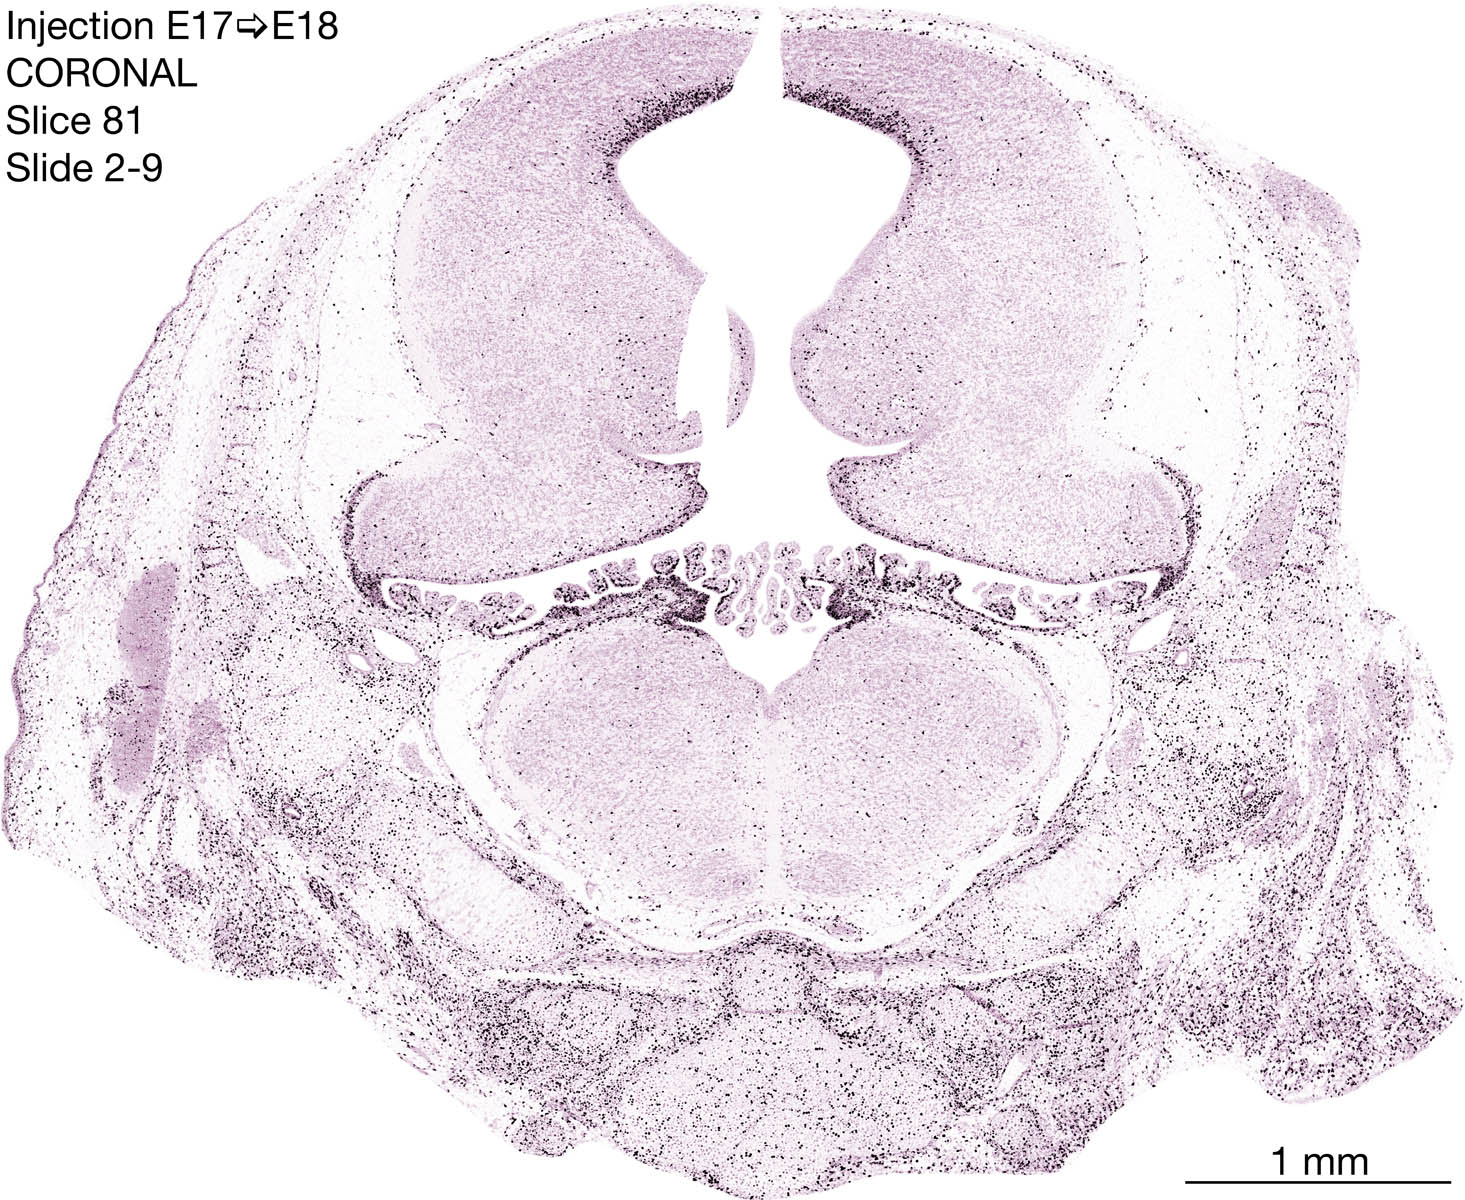

E17 to E18 Survival Archived Images-Coronal

The following images are from a coronally-sectioned head of an E18 rat embryo exposed to tritiated thymidine on E17–24 hr survival.  Note the heavily-labeled cells just outside the germinal zones are now mainly in the diencephalon and forebrain.  These are postmitotic young neurons generated ON E17.  Note that the banded labeling is prominent outside the neocortical neuroepithelium.  Many of the germinal zones in the brainstem have become transformed into the primitive ependyma, and the entire brainstem is becoming more mature; the only primitive area is the cerebellum, where the external germinal layer is now more prominent.